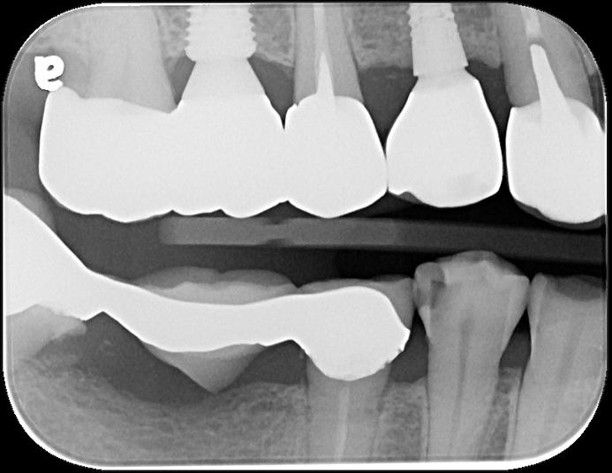

治療前,蛀牙卡食物

治療前,嚴重鄰接面蛀牙